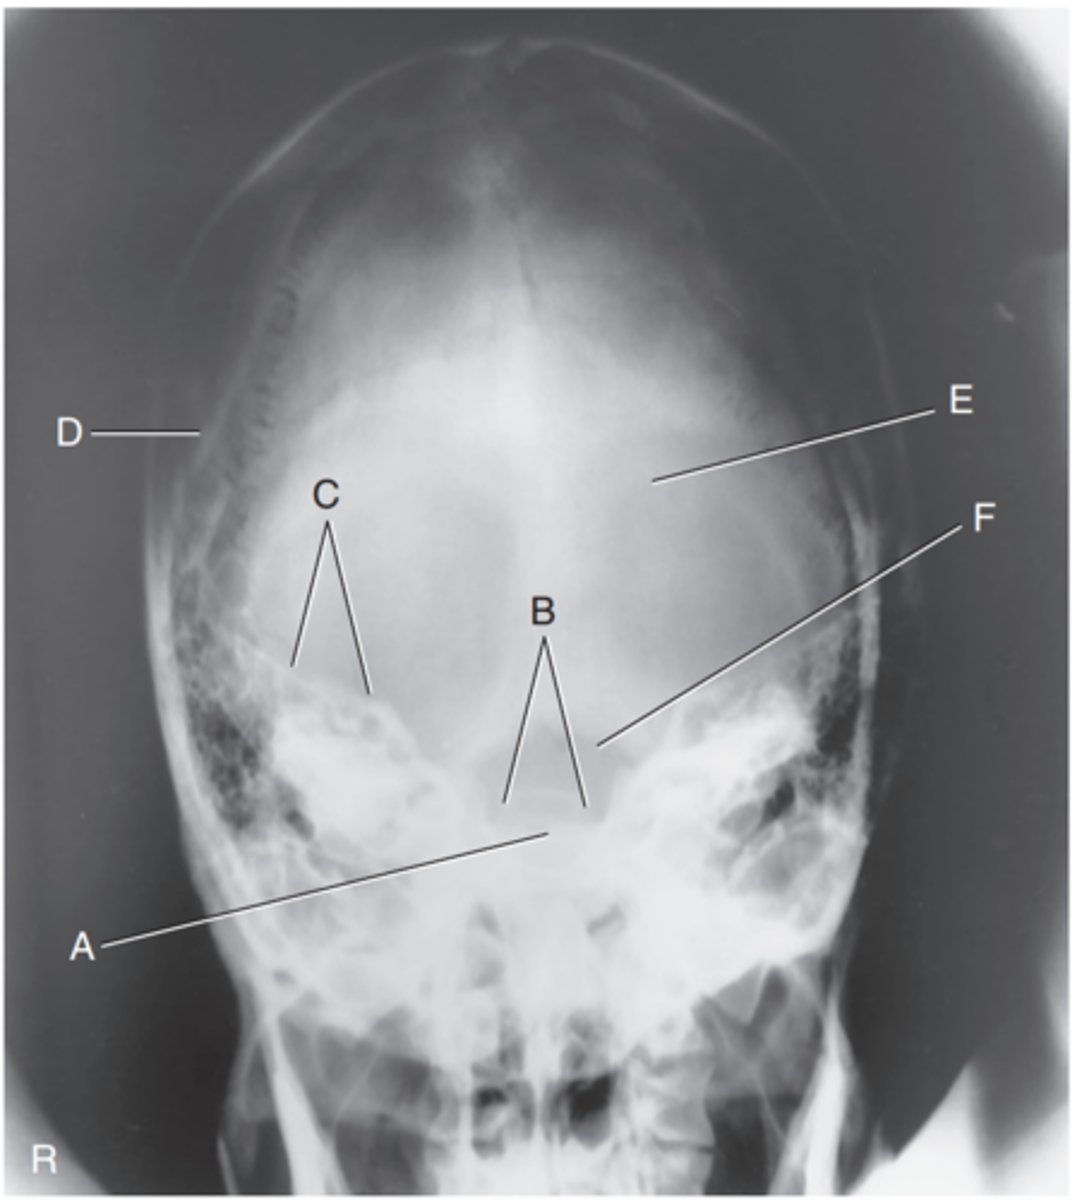

Supraorbital margin of right orbit

Label A

Crista galli of ethmoid

Label B

Sagittal suture

Label C

Lambdoidal suture

Label D

Petrous ridge

Label E